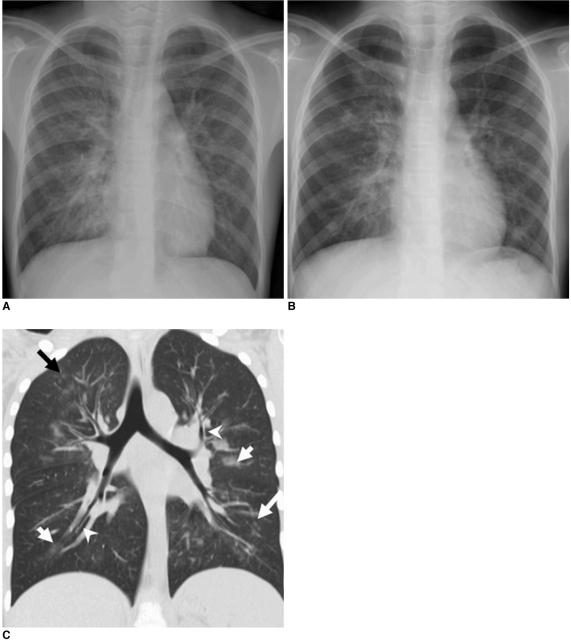

The initial chest radiograph was normal in 384 of 410 (94%) patients and abnormal in 26 of 410 (6%) patients. Parenchymal abnormalities seen on the initial chest radiographs included prominent peribronchial marking (25 of 26, 96%), consolidation (22 of 26, 85%), and ground-glass opacities without consolidation (2 of 26, 8%). The involvement was usually bilateral (19 of 26, 73%) with the lower lung zone predominance (22 of 26, 85%). Atelectasis was observed in 12 (46%) and pleural effusion in 11 (42%) patients. CT (n = 6) scans showed peribronchovascular interstitial thickening (n = 6), ground-glass opacities (n = 5), centrilobular nodules (n = 4), consolidation (n = 3), mediastinal lymph node enlargement (n = 5), pleural effusion (n = 3), and pneumomediastinum (n = 3).

Abnormal chest radiographs were uncommon in children with a swine-origin influenza A (H1N1) virus (S-OIV) infection. In children, H1N1 virus infection can be included in the differential diagnosis, when chest radiographs and CT scans show prominent peribronchial markings and ill-defined patchy consolidation with mediastinal lymph node enlargement, pleural effusion and pneumomediastinum.

410 名患儿中,384 名(94%)患儿的初始胸部 X 射线正常,26 名(6%)患儿异常。最初的胸部 X 射线显示的实质异常包括明显的支气管周围标记(26 例中的 25 例,96%)、实变(26 例中的 22 例,85%)和无实变的磨玻璃样混浊(26 例中的 2 例,8%)。病变通常是双侧的(26 例中的 19 例,73%),下肺区为主(26 例中的 22 例,85%)。12 例(46%)患儿出现肺不张,11 例(42%)患儿出现胸腔积液。CT(n=6)扫描显示支气管血管周围间质增厚(n=6)、磨玻璃样混浊(n=5)、小叶中心结节(n=4)、实变(n=3)、纵隔淋巴结肿大(n=5)、胸腔积液(n=3)和气胸(n=3)。

儿童感染猪源甲型流感(H1N1)病毒(S-OIV)时,异常胸部 X 射线并不常见。当胸部 X 射线和 CT 扫描显示明显的支气管周围标记和边界不清的斑片状实变,伴纵隔淋巴结肿大、胸腔积液和气胸时,可将 H1N1 病毒感染纳入鉴别诊断。